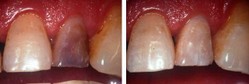

Blanqueamiento Dental

Técnicas conservadoras para la resolución y mejoramiento estético de la coloración de una o varias piezas dentarias.